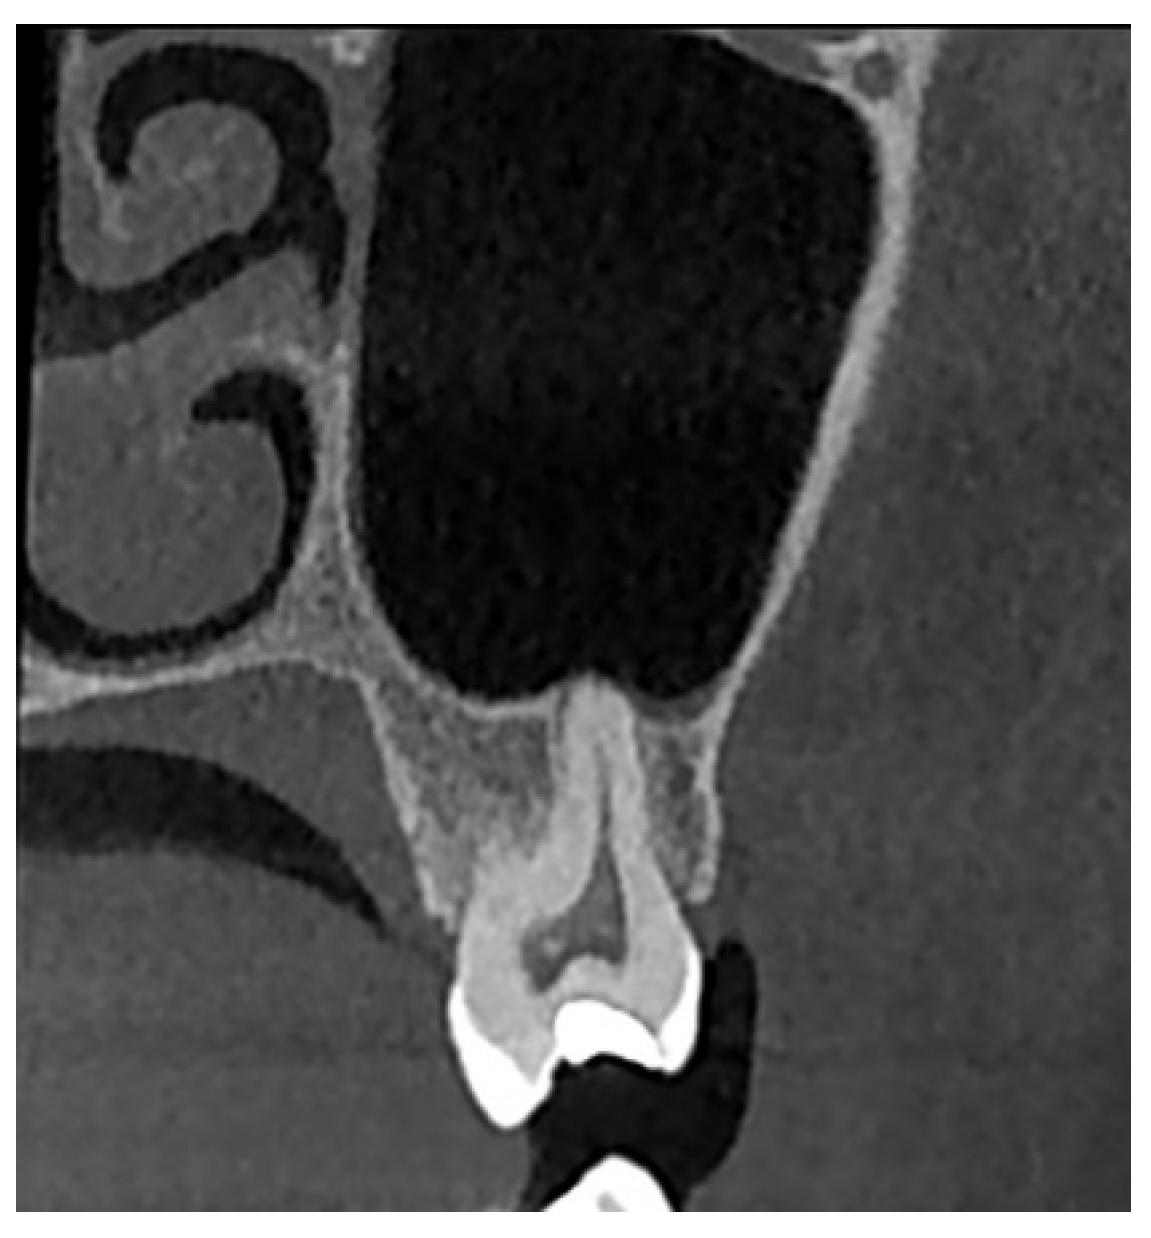

- Type I: Penetrating relationship—the tooth root extends into the maxillary sinus cavity (Figure 2).